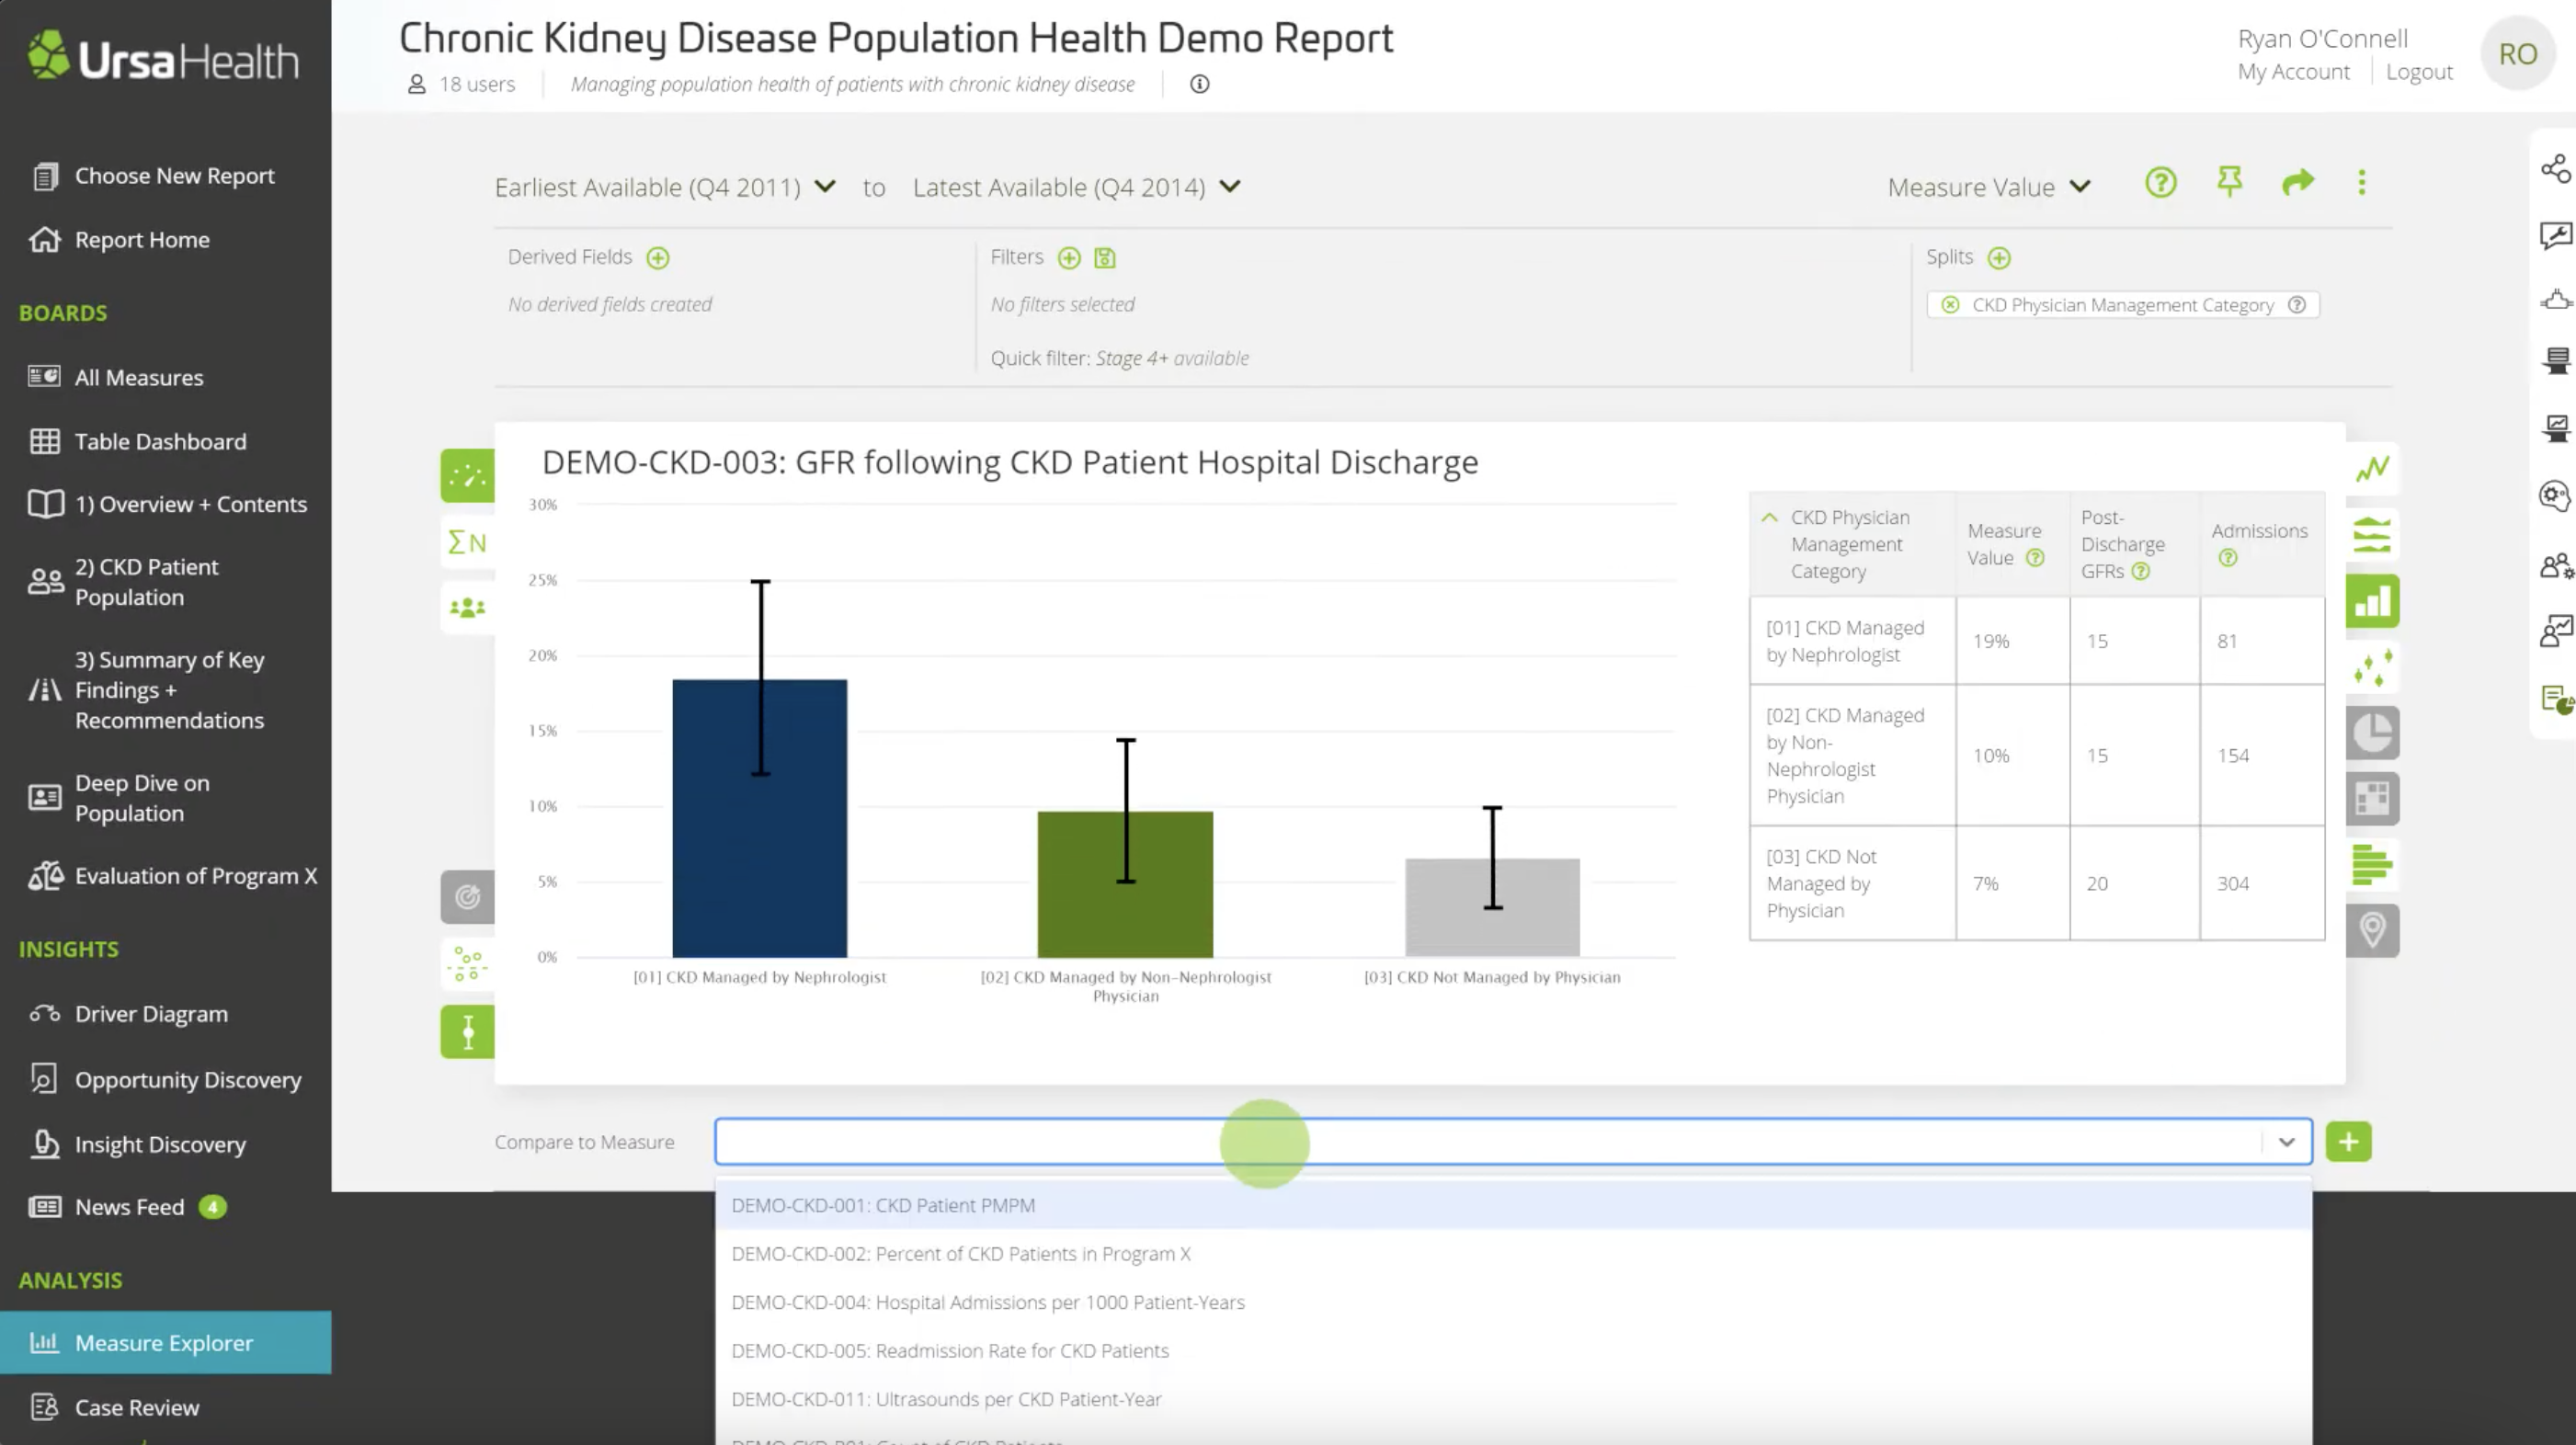

Healthcare organizations creates an analytics development platform that helps you quickly find value in your rich data resources.

Our mission is to create an explainer for Ursa Health database system, an easier access for for the clinical, financial, and operational use.

EXPLAINING VISUALIZATION